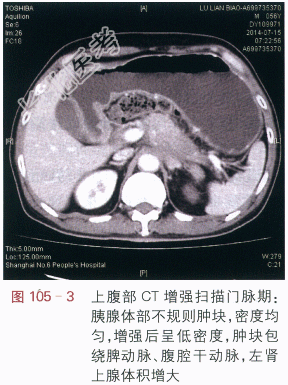

影像学资料如图105-1~图105-4所示。

读片分析:上腹部CT平扫显示胰腺体部增大,密度均匀,尾部萎缩,胰腺周边模糊(见图105-1),增强扫描动脉期:胰腺体部不规则肿块,增强后动脉期呈低密度,肿块边缘不清,肿块包绕脾动脉、腹腔干动脉(见图105-2);门脉期:胰腺体部不规则低密度肿块,肿块包绕脾静脉(见图105-3)。延时期肿块密度呈低密度,肿块包绕腹腔血管、并向周边侵犯,左肾上腺体积增大(见图105-4)。